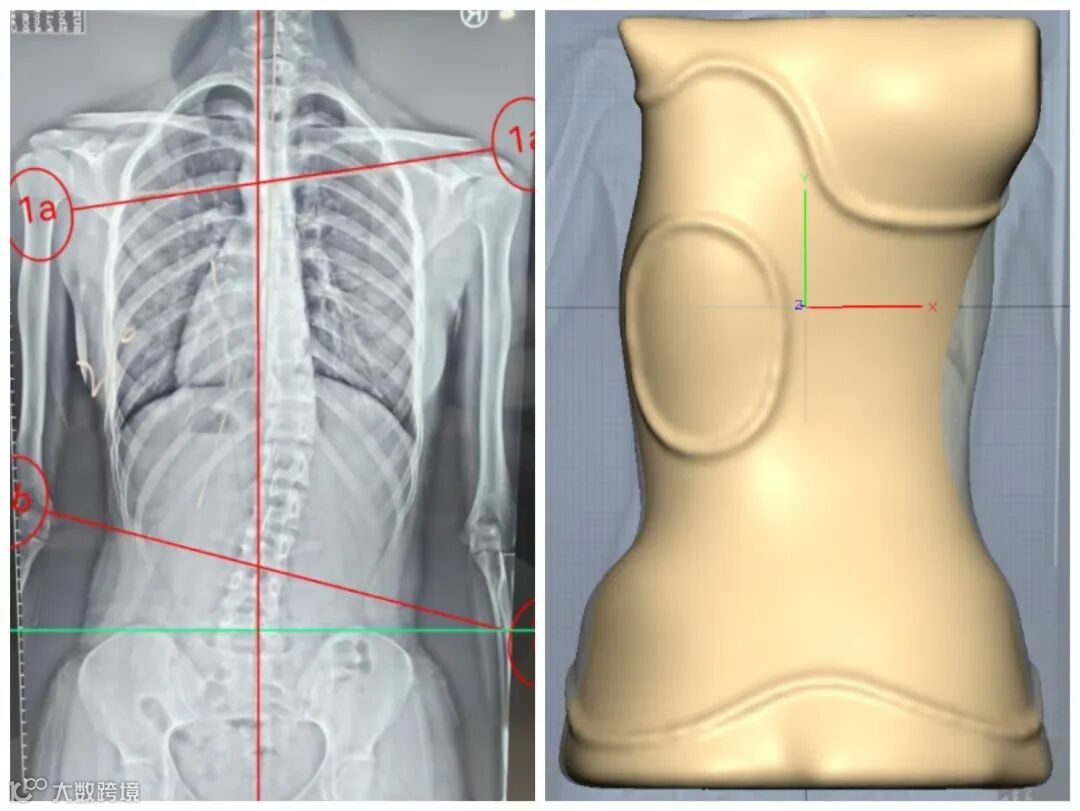

周同学全脊柱正侧位X片,躯干向右偏移。